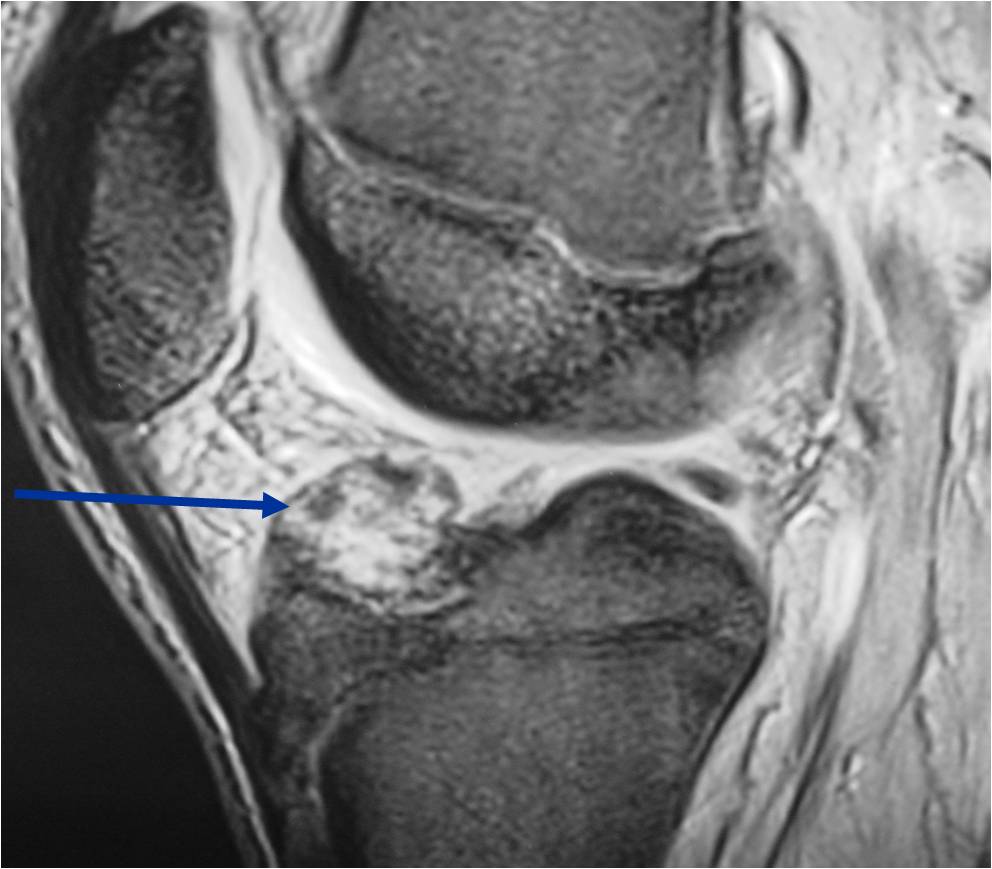

General Information Enchondroma is a benign indolent intramedullary hyaline cartilage neoplasm Accounts for 10% of all benign osseous tumors Limited growth, most lesions are less than 5 cm in maximal dimension Bones grow from a cartilaginous growth plate that...